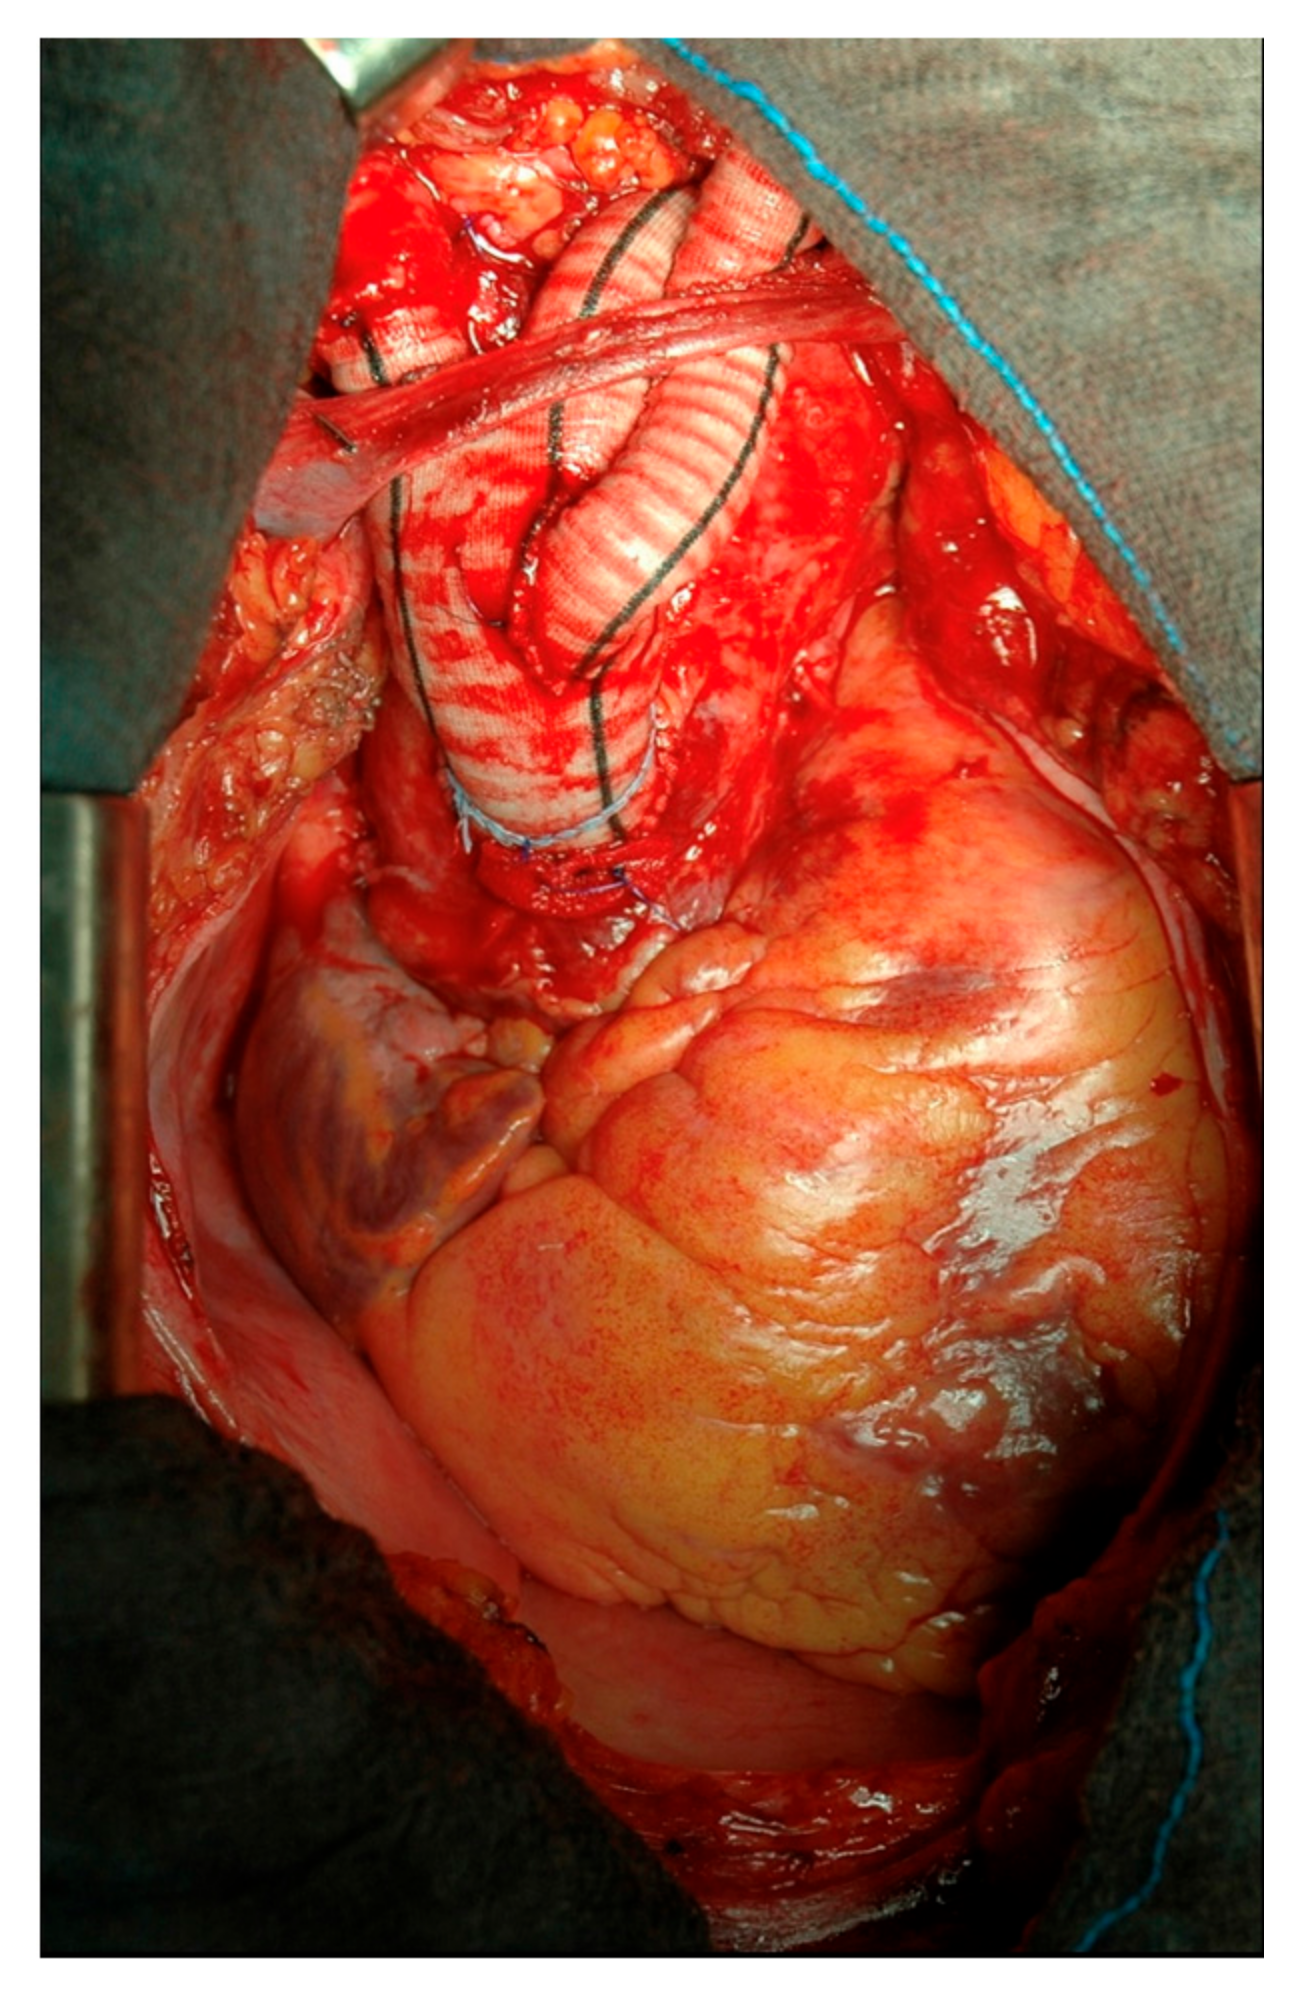

2.1. Surgical Technique

2.2. Type I Debranching

2.3. Type II Debranching

2.4. Branched Graft Position